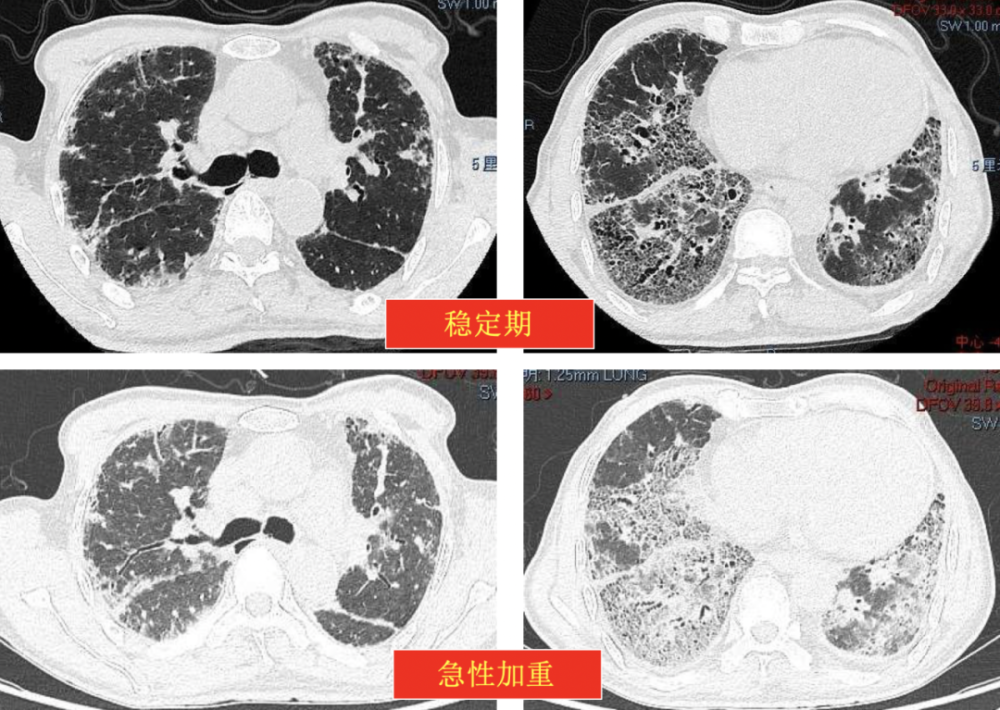

3、肺结核纤维化是肺结核在恢复过程中,肺部组织因炎症和损伤修复后形成的一种病理改变其核心机制是肺结核杆菌感染引发的免疫反应,导致肺泡结构破坏,成纤维细胞增生并分泌胶原蛋白,最终形成瘢痕组织这种纤维化可能影响肺部功能,但程度因病变范围而异主要病因肺结核杆菌感染是直接诱因当病原体侵入;核心机制与成因肺结核纤维化的根本原因是结核分枝杆菌感染引发的肺部炎症反应当病原体侵入肺部后,免疫系统通过释放炎性因子清除病菌,但此过程会破坏肺泡结构及肺间质在修复阶段,由于损伤范围较大,肺部组织无法完全恢复原有结构,转而以纤维组织替代受损区域,形成瘢痕样改变这种纤维化是机体对严重;肺纤维化是一种以肺组织结构破坏为特征的间质性肺疾病终末期改变,其核心机制涉及成纤维细胞异常增殖和细胞外基质过度沉积具体可从以下方面理解1 病理特征肺纤维化的本质是肺间质支持肺泡的气体交换结构发生不可逆的纤维化重塑正常肺组织由弹性纤维和少量成纤维细胞构成,而纤维化过程中,成纤;这些因素共同作用下,成纤维细胞过度增殖并分泌大量胶原蛋白,取代正常的肺泡结构,形成瘢痕组织临床表现方面,轻度肺纤维化患者可能无明显症状,仅在剧烈运动后出现轻微气短或干咳,对日常生活影响较小这一阶段,肺部功能虽已受损,但尚未达到严重影响气体交换的程度诊断主要依赖胸部高分辨率CT检查,可。

4、1 病理特征肺纤维化的本质是肺间质支持肺泡的气体交换结构发生不可逆的纤维化重塑正常肺组织由弹性纤维和少量成纤维细胞构成,而纤维化过程中,成纤维细胞被异常激活,大量分泌胶原蛋白等细胞外基质,导致肺组织逐渐硬化瘢痕化这种结构改变会破坏肺泡毛细血管膜的完整性,使气体交换效率显著下降;胸片X线表现为双肺底和周围分布的弥漫性网格状蜂窝状阴影可能伴或不伴牵拉性的支气管扩张肺功能诊断肺功能检查通常诊断为限制性通气功能障碍疾病发展病情一般呈进行性发展,若不及时治疗,最终可能因呼吸衰竭导致死亡综上所述,特发性肺纤维化是一种严重的慢性间质性肺疾病,具有特定的病理;肺纤维化是指支撑肺泡的肺间质发生纤维化,是肺部组织在多种因素作用下出现异常修复和重塑,导致正常肺组织结构被破坏纤维组织增生的疾病状态具体而言,肺纤维化过程中,肺部的正常细胞和结构被纤维组织取代,使得肺脏逐渐失去弹性,变得僵硬这一过程类似于柔软有弹性的海绵慢慢变成硬邦邦的石头,导致;肺纤维化的发生主要与以下三类因素相关环境因素长期暴露于有害环境是重要诱因例如,吸入大量粉尘如石棉硅尘或化学物质如博来霉素胺碘酮等药物,以及某些工业化学物质,这些物质会直接损伤肺部,引发炎症反应若未及时干预,炎症反复刺激可能导致肺间质纤维化疾病因素自身免疫性疾病如类风湿关节炎系。